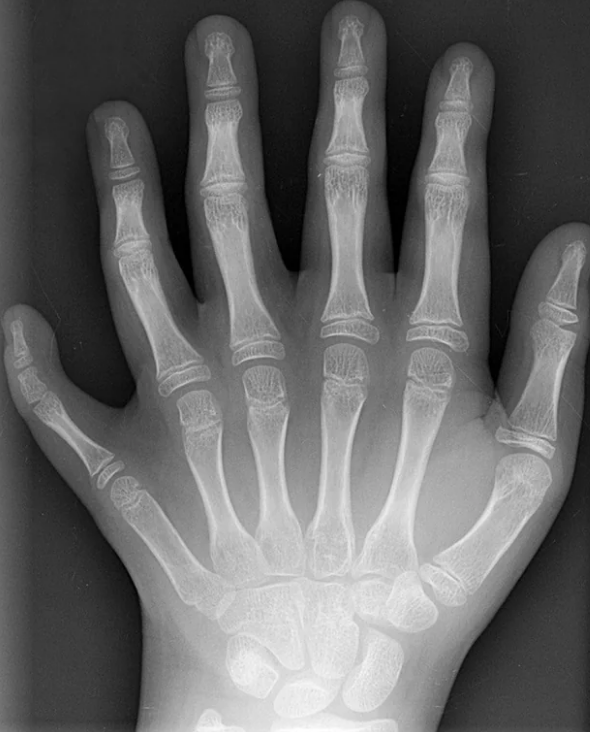

35.Here’s what an x-ray looks like for someone with six fingers.